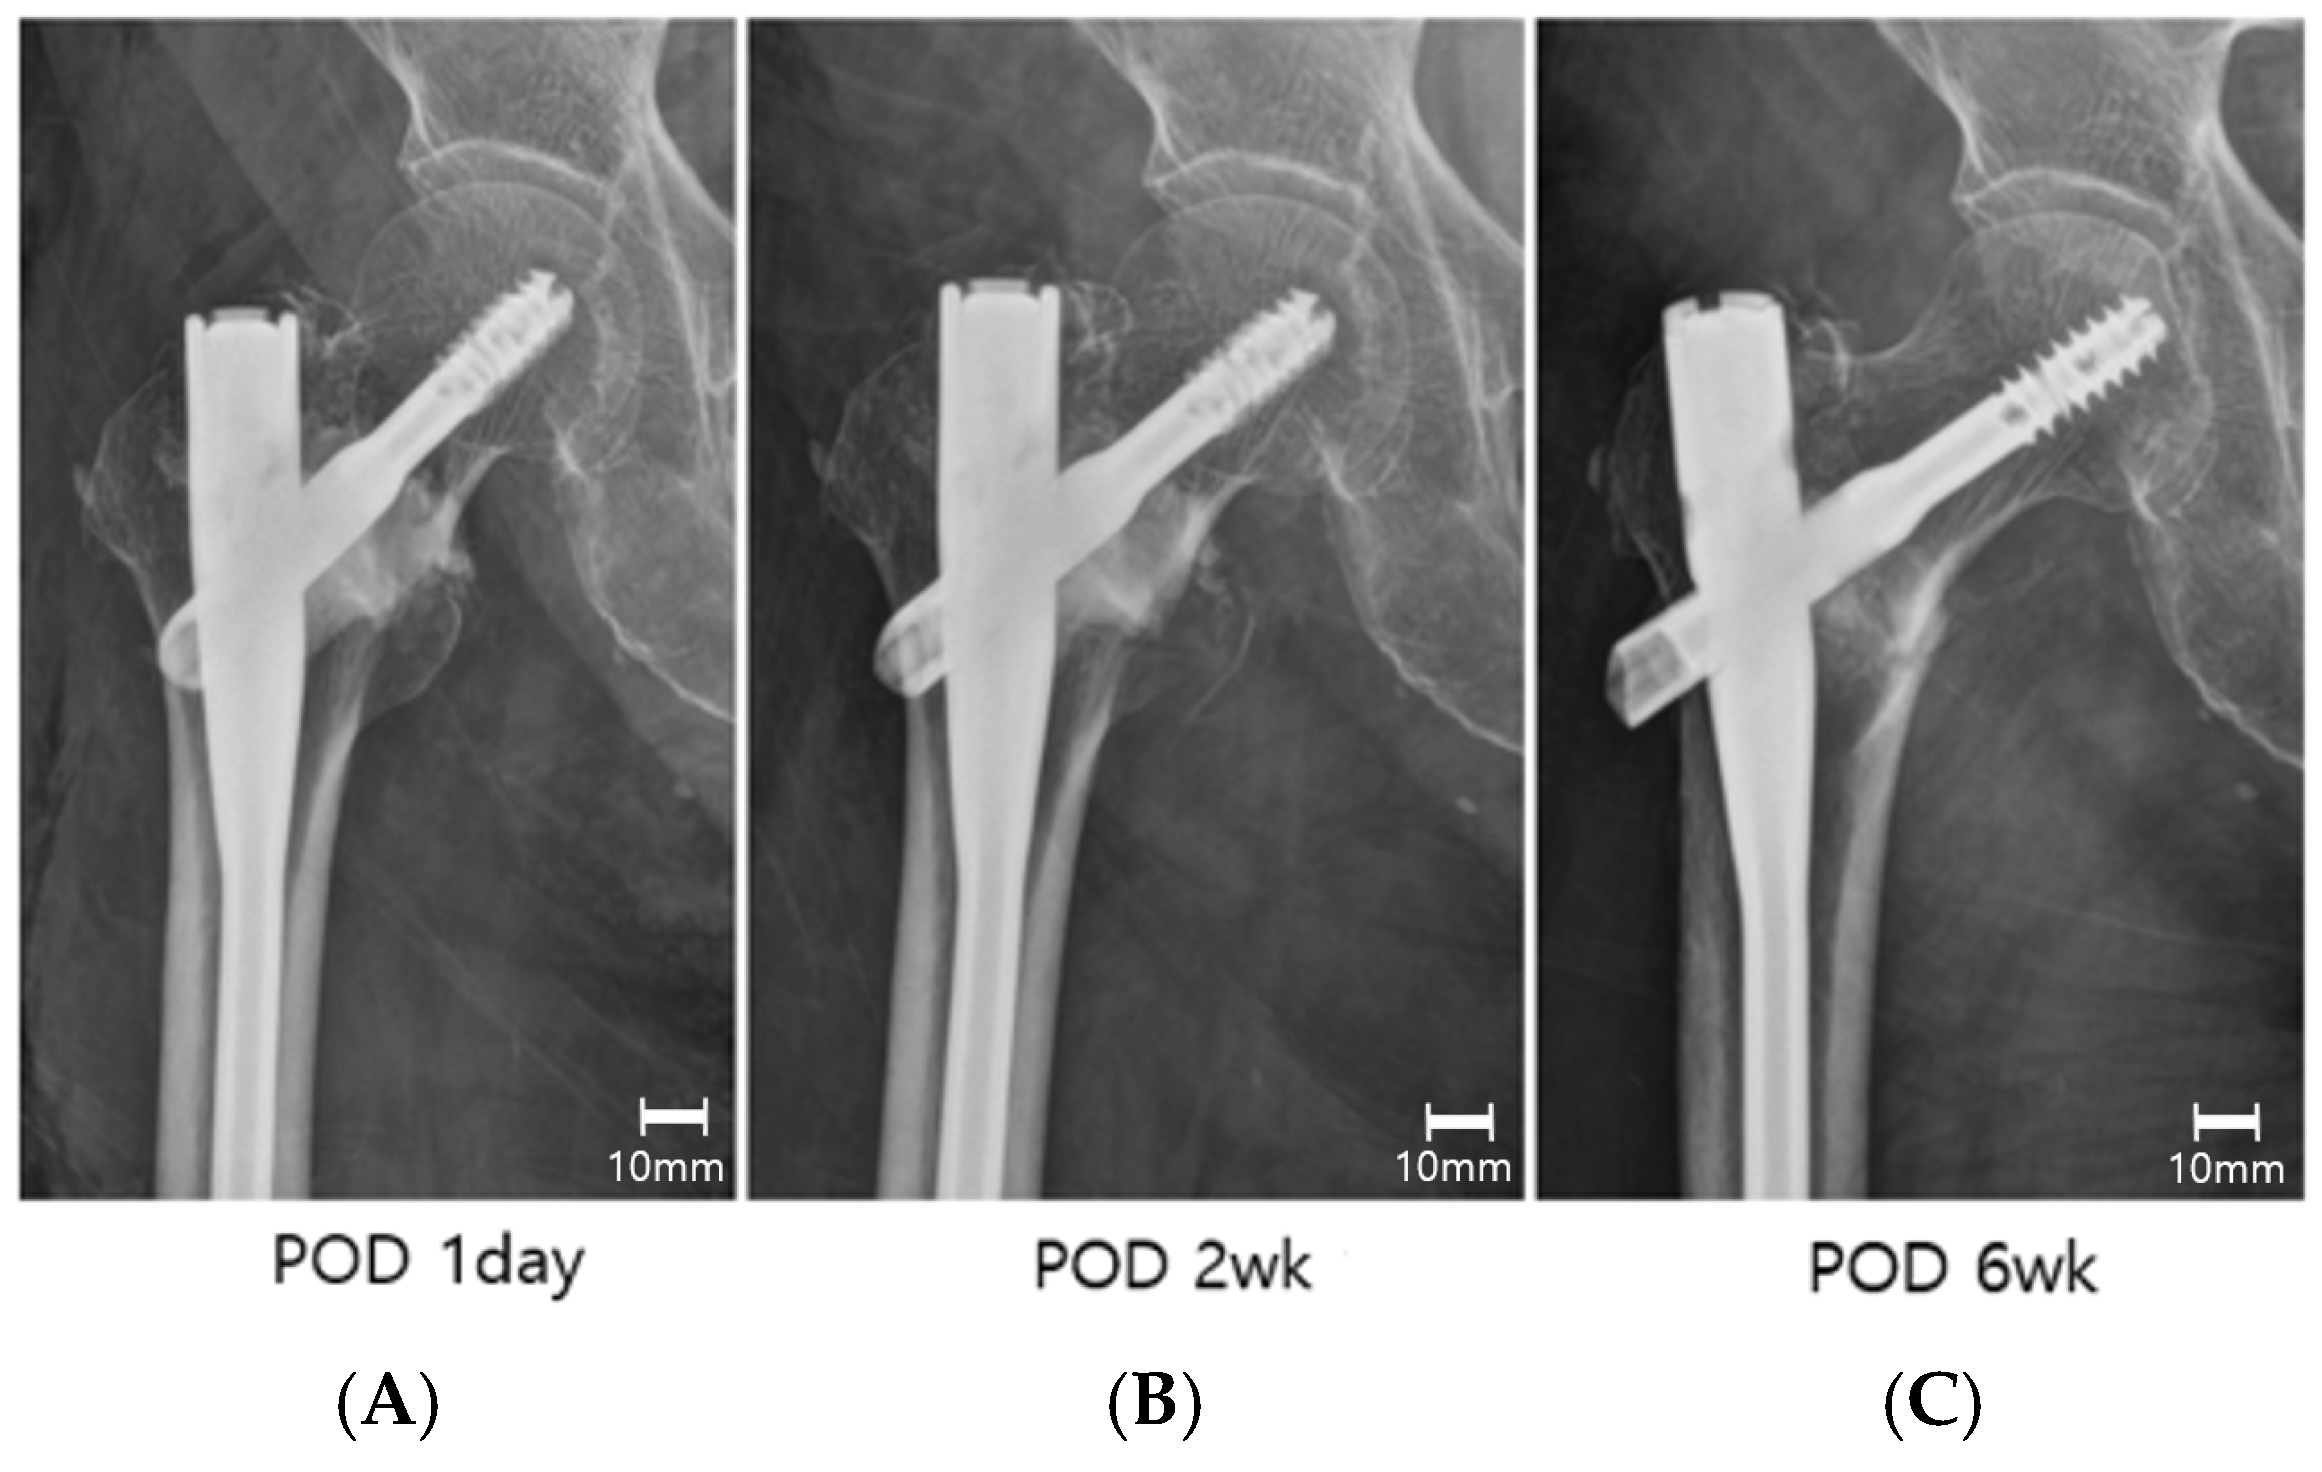

| Lagscrew sliding, mm (mean ± SD) | 2.8 ± 2.1 | 5.4 ± 3.2 | 0.01 * |

| Varus collapse (Δ neck–shaft angle), degrees (mean ± SD) | 3.3 ± 4.6 | 8.2 ± 5.3 | 0.02 * |